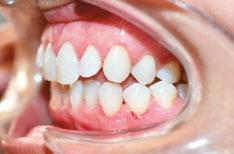

Patient J, a 39-year-old female, (Figures 1, 2, 3, 4, 5, 6) came to the office with concerns about difficulties chewing food and experiencing dry mouth upon waking up in the morning. Additionally, her partner was disturbed by her snoring. Upon examination, several issues came to light:

1. An open bite in the anterior region and a posterior crossbite

2. Breathing through the nose 10% of the time.

3. Lips and cheek muscles actively helping with swallowing food and drinks

4. Lips open 100% of the time

5. Tongue cannot maintain position on a spot, moves between teeth upon swallowing

6. Tongue thrust

7. Weak control over soft palate

Muscle tension around the temporomandibular joint (TMJ) was also evident5 as well as mandibular bilateral lingual torus as response to constant occlusal pressure applied during bruxism.

Figure 2: Anterior view before treatment

Figures 3 and 4: 3. Right side before treatment. 4. Left side before treatment